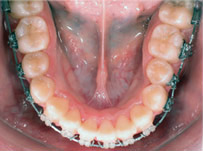

齒列擁擠的不正咬合經由擴大效果排列整齊:

Before

Proceeding

After